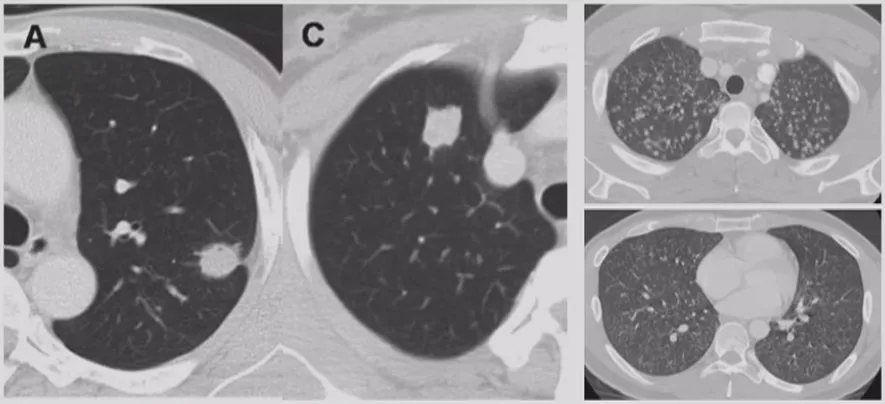

在临床上经常手术切除后发现是AAH,关于AAH的病人是否需要手术还存在很大的争议,有的认为不需要手术,观察就可以。那么我们在术前怎么评判是否为AAH?其实具有一定特征。一般来说,多位于肺外周,多<5mm,圆形或类圆形,边界清楚,多发更常见,绝大部分是均匀的纯磨玻璃影,里边没有实性成分。组织学检查AAH呈轻度到中度非典型立方柱状上皮细胞沿肺泡和呼吸性细支气管上皮增殖,无浸润,这样在临床上诊断AAH应该没有问题。但是,如下图所示,这个病人是多灶性病变,现在多灶性结节有所增多,会给临床的处理上带来一定压力。

动静脉畸形

还有一点要提醒大家的就是血管畸形。多表现为圆形或轻度分叶的致密影,多位于肺门附近的肺内带,增强扫描时病变区强化明显供应动脉及引流静脉更加清晰。所以现在有的病人发现了结节,还是有必要做增强CT,为什么?如果你觉得这个结节没做过增强CT,靠活检、胸腔穿刺或者导航,如果病人是血管畸形,那必然会大出血,要面临很严重的并发症。所以对于结节病人,如果你采用介入性的或者是侵入性的诊断方法时,需谨慎一些,为了防止活检大出血,最好做个增强CT以观察。